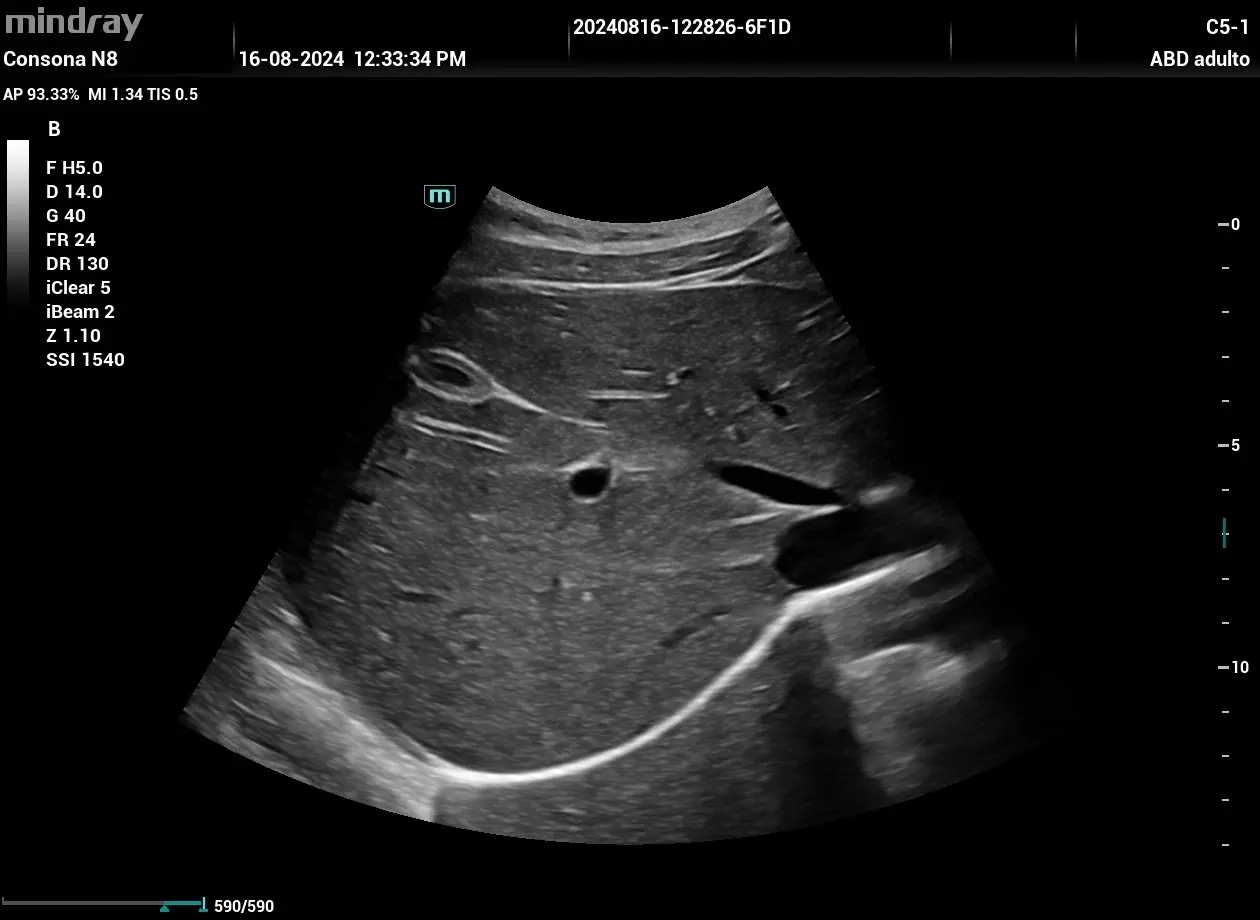

Realización de una ecografía abdominal